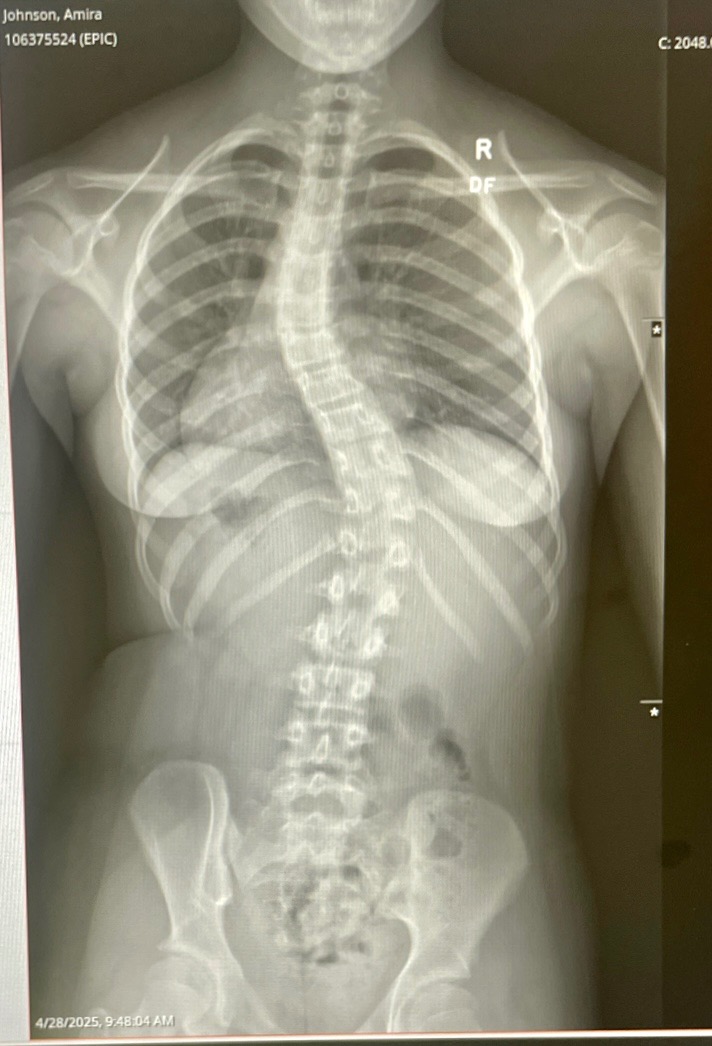

Amira is a passionate dancer, cheerleader, pageant competitor, and contortionist with scoliosis. Diagnosed at 9 years old, she was placed under a “wait and see” plan with her pediatric orthopedic team. Unfortunately, her condition has rapidly worsened and progressed to an S-shaped spinal curve measuring 38degrees. Additionally, she has a knee-length discrepancy caused by her scoliosis that is further complicating her condition.